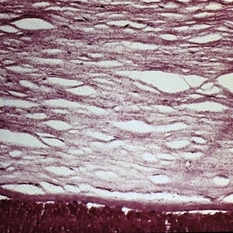

Subepithelial bullae in ocular pemphigoid.

Condition/keywords: subepithelial bullae